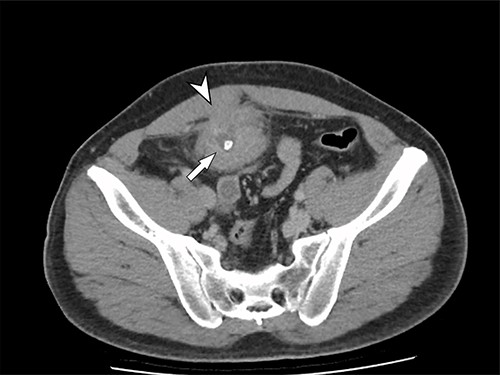

A 41-year-old, previously well, male presented to the emergency department with lower abdominal pain, pyrexia with a temperature of 38.2°C and a palpable suprapubic mass. His relevant background history included an uneventful laparoscopic appendicectomy 2 years prior for acute appendicitis, insulin independent type 2 diabetes and hypertension. He presented with raised inflammatory markers and computed tomography (CT) showing a well circumscribed central pelvis lesion that appeared concerning for a urachal malignancy (Fig. 1). This lesion was closely associated with the dome of the bladder (Fig. 2). This supracystic lesion measured 58 mm × 56 mm with central cystic component of 15 mm in diameter, and contained a 11 mm central calcification. Further characterization with magnetic resonance imaging showed possible extension of this mass to the rectus abdominis without significant lymphadenopathy (Fig. 3). Flexible cystoscopy only found inflammation at the dome. As urachal malignancy could not be unequivocally excluded on imaging studies alone, following multidisciplinary discussion, the decision was made to perform an excision of this lesion.

Sagittal CT cystogram. Arrowhead indicates involvement of anterior abdominal wall. Arrow indicates association of lesion with the dome of the bladder.